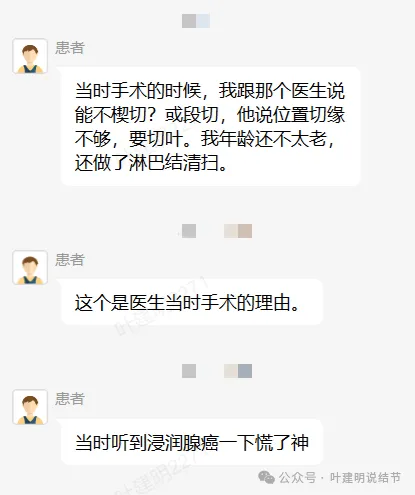

我问结友是楔切还是叶切,因为手术前急着咨询我怎么切的事。当时不是已经明确告诉她先楔切,如果没有高危亚型的话,就加淋巴结采样,不要切肺叶。而且从影像上已经告诉她考虑是浸润性腺癌了的,我判断腺泡为主型可能性大。结果说是切了肺叶!

那之前的问诊不是白问了吗?有何意义呢?我是觉得很可惜的。结友回复说,当地医生没有认真谈手术方案,那你要自己提出来呀!医生只说先切一下,看看是不是恶性,结果术后就是肺叶切掉了!合乎指南吗?当然合规的,这是奉旨切肺叶呀!因为指南的表述就是:早期肺癌的标准术式是解剖性肺叶切除加淋巴结清扫术,是1A类证据级别的!

医生说这位置亚肺叶切除切缘不够!!这是啥判断?还说年纪比较轻,还做淋巴结清扫。当然清扫也没错,也是规范的。这该死的指南!!